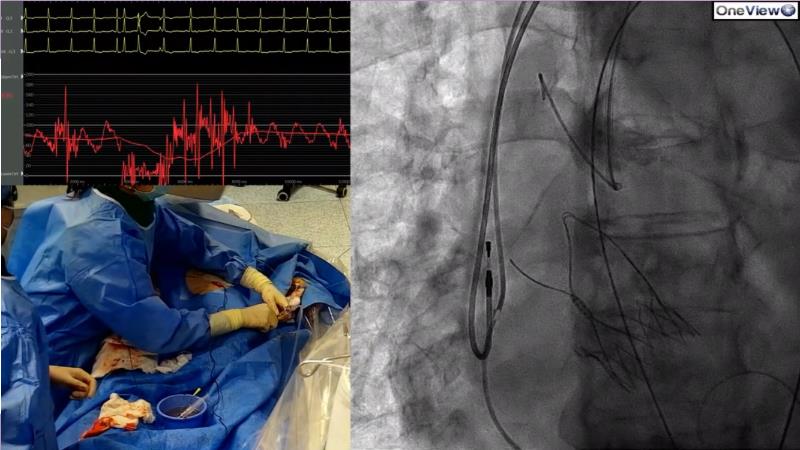

Watch this session if you want to learn more about the BENCHMARK Registry and its key findings, explore how patients can benefit from optimised TAVI programmes, get an idea of how challenging Redo-TAVI will be for everyday practice in the future, and to view a LIVE redo-TAVI case.